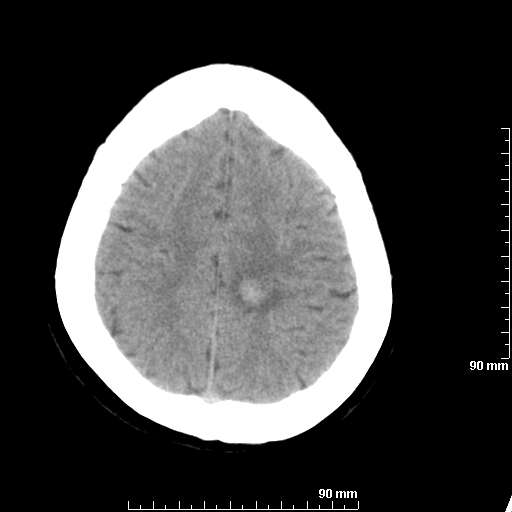

我院西门子单排CT由于一零件受损而产生的伪影.

哈哈,都不是。是虑线器fiter裂损。大家没想到吧。

哦,跟脑出血有点像哦

形状不规则,边缘模糊。比较特殊的一种伪影哈!

这种伪影很常见!伪影应该是在视野的中心的。

西门子的虑线器fiter裂损这才是很难见的问题,GE的最常见

虑线器老化,中间崩裂一块掉了